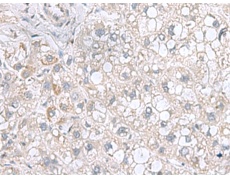

IHC positive control: |

Human liver cancer |

IHC Recommend dilution: |

100-200 |